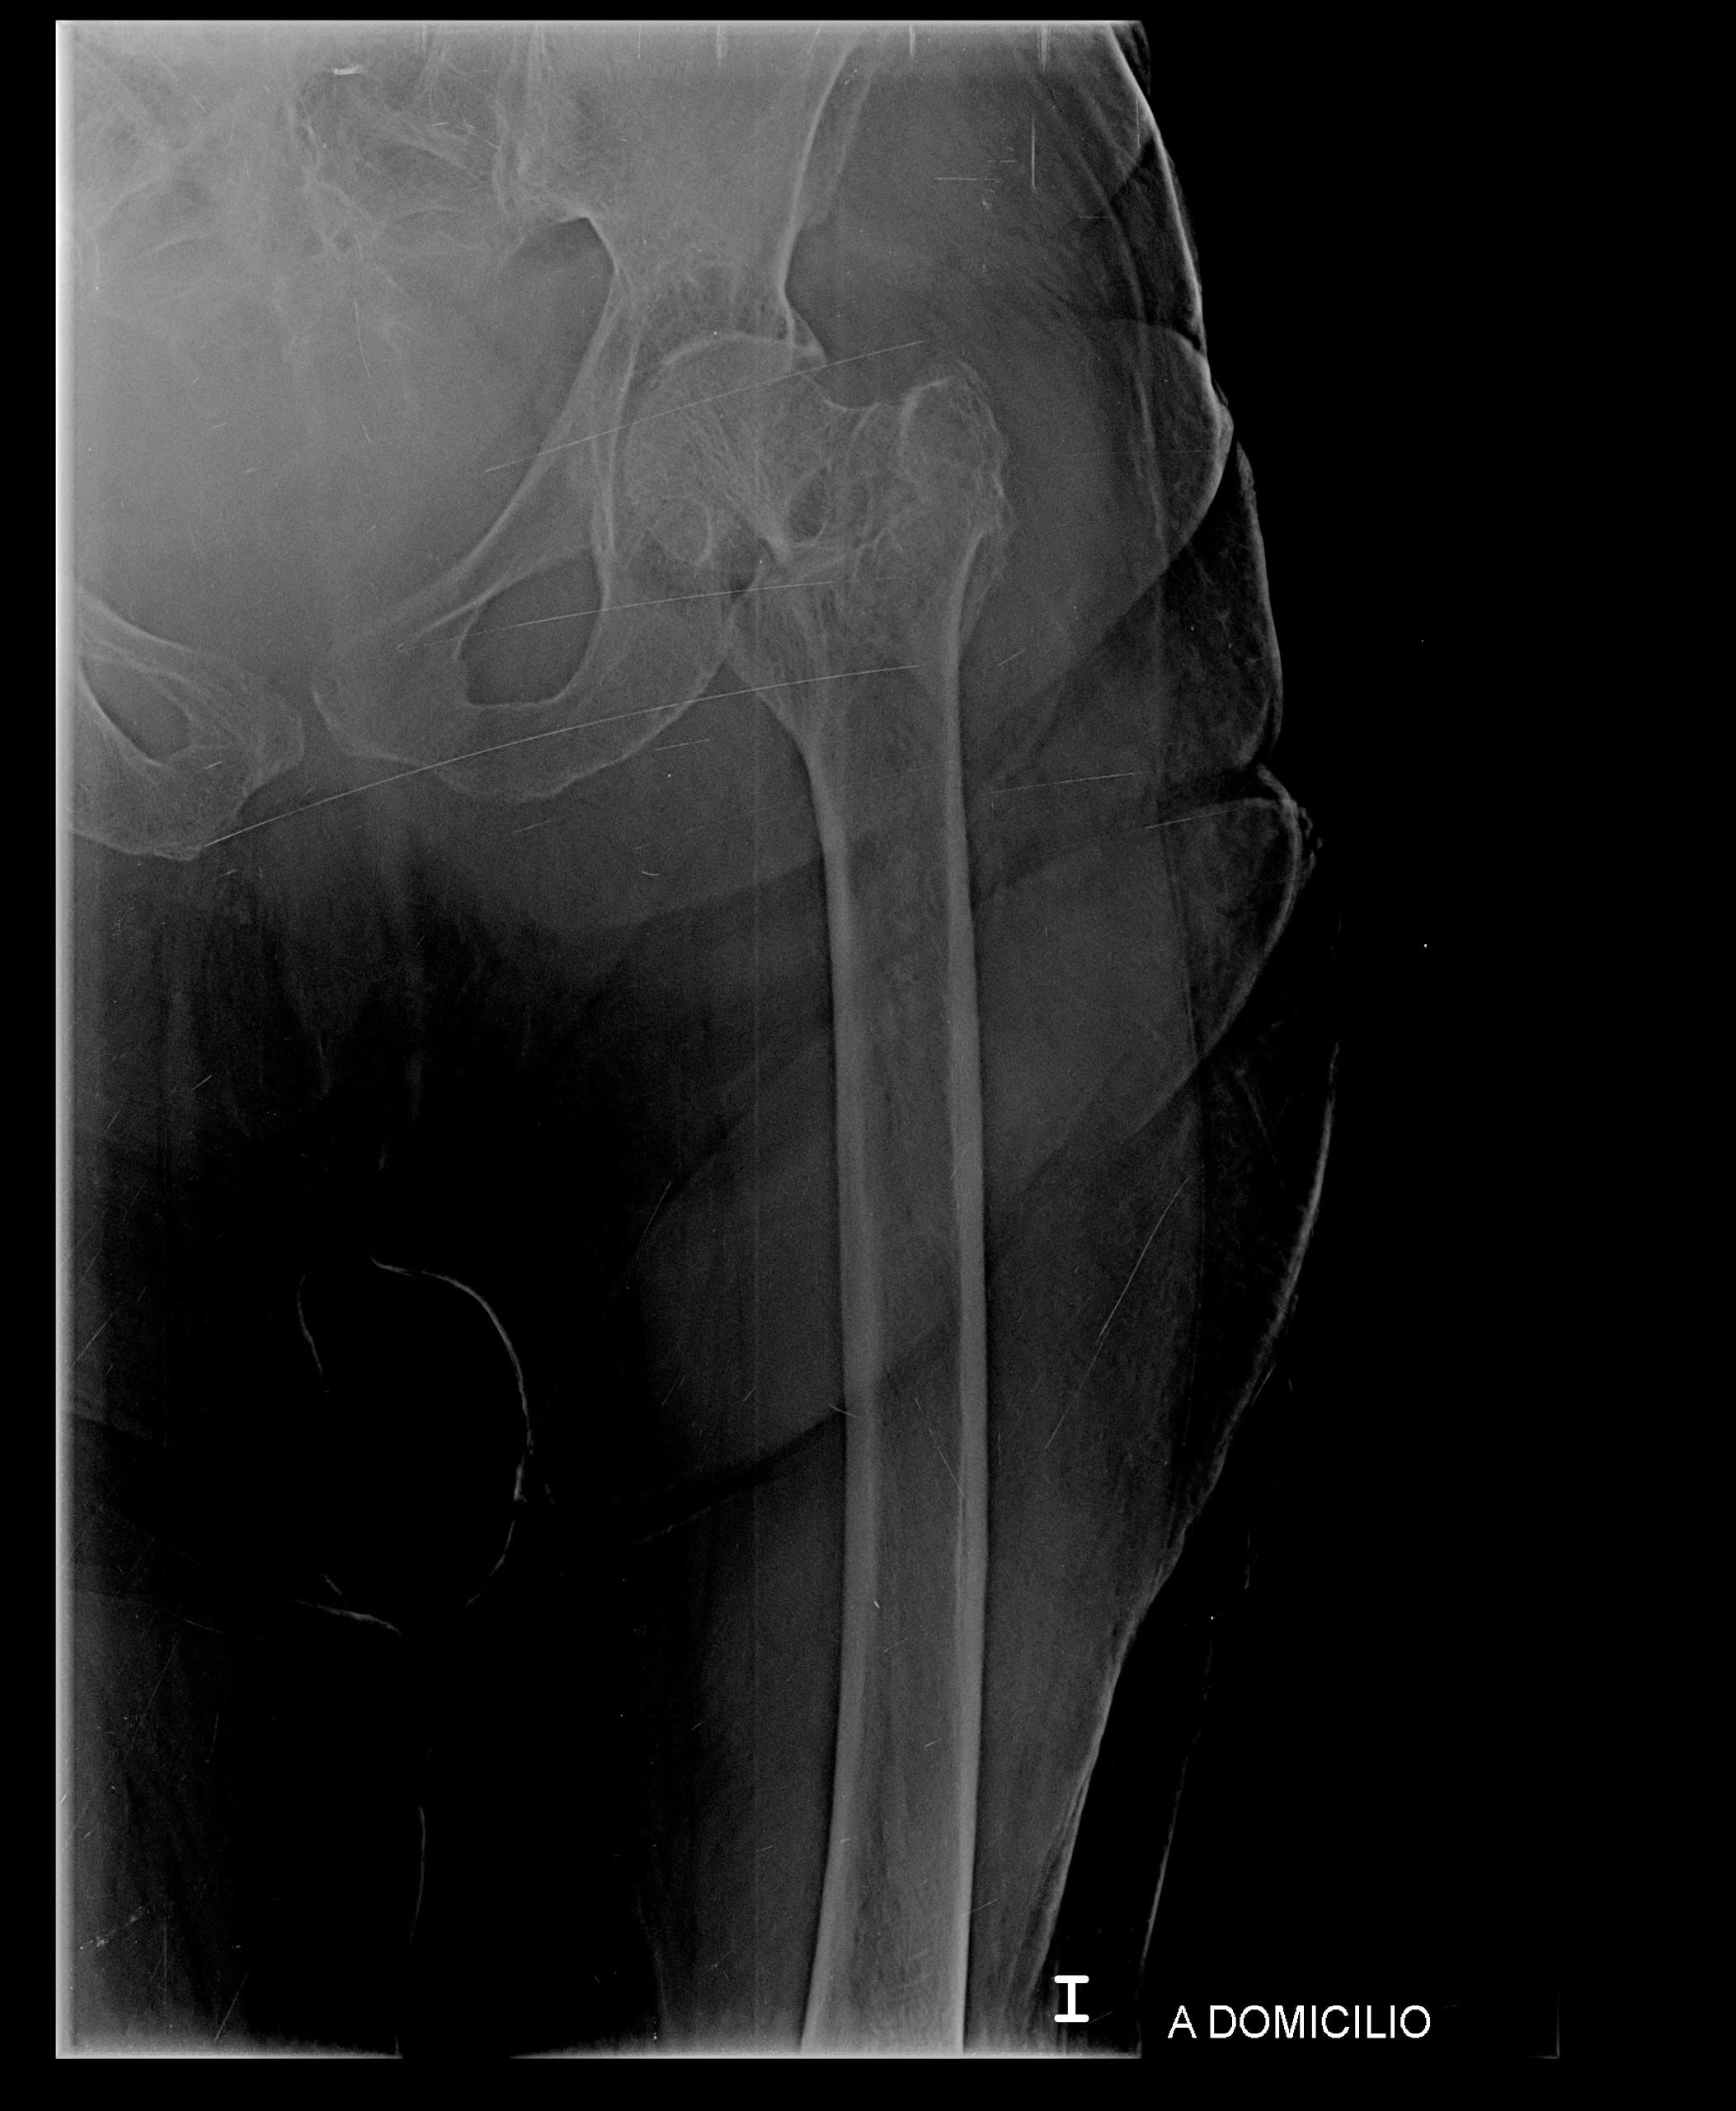

Recently, my grandmother suffered a terrible fall and fractured her left femur. She now requires extensive surgery to replace the femur, and the medical expenses are overwhelming. Our family is doing everything we can to support her, but the costs of the surgery, hospital care, and recovery are far more than we can manage alone.

Recientemente, mi abuela sufrió una fuerte caída y se fracturó el fémur izquierdo. Ahora necesita una cirugía extensa para reemplazar el hueso, y los gastos médicos son abrumadores. Aunque nuestra familia está haciendo todo lo posible para apoyarla, los costos de la cirugía, la atención hospitalaria y la recuperación superan lo que podemos manejar solos.